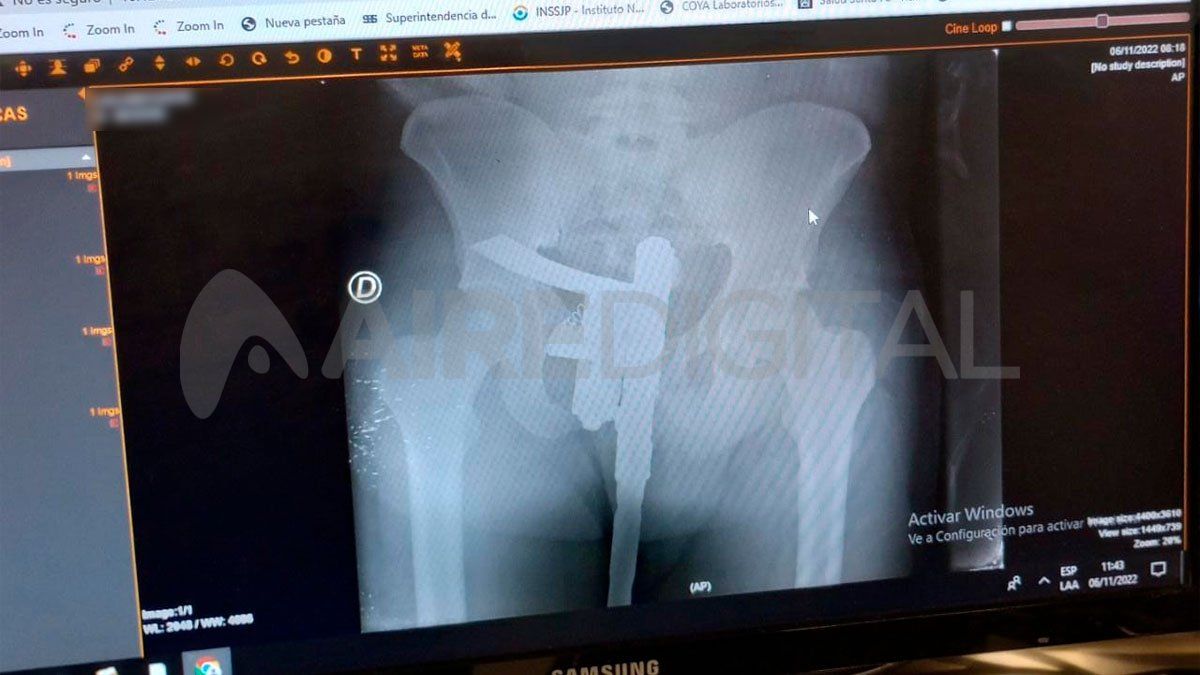

El desconcierto comenzó con los controles de rutina. Con el fin de definir su estado de salud, los profesionales de la salud trasladaron al paciente a la sala de rayos x. Allí, detectaron la presencia de un arma de fuego en los genitales del hombre que no había sido declarada.